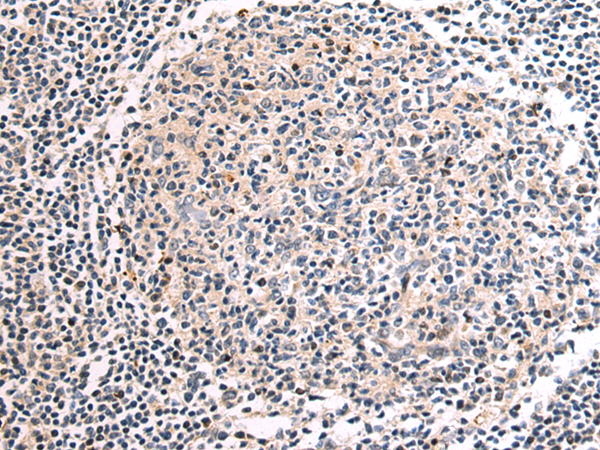

分类: 科研抗体货号: P10113别名: EIF2B; EIF-2Bbeta应用: IHC反应种属: Human, Mouse, Rat